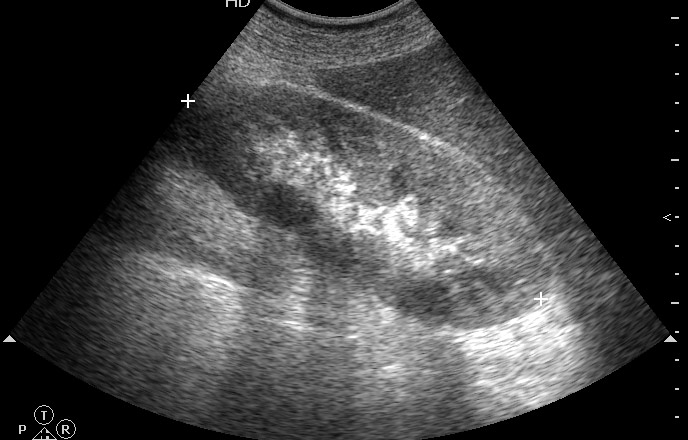

Поперечное сканирование правой почки на уровне верхней трети.

очень похоже на абсцесс в в/3 правой почки,по поводу паранефрита сомнительно,хотя и намечается перипроцесс на третьем скане.

Похоже на абсцесс "прорывающийся" субкапсулярно:отграниченый с толстыми неровными стенками и гипоэхогенной зоной в центре-"расплавление"ткани?(inflamatory рseudotumor) или же renal cell carcinoma с диструкцией в центре(но...скудновата клиника для обоих случаев,ведь нету фона,как сахарный диабет,глубокая старость...),если субфебрилитет,то может быть формирующаяся каверна? Все нуждается в дообследовании-КТ

Острый правосторонний пиелонефрит, абсцесс (карбункул) почки.